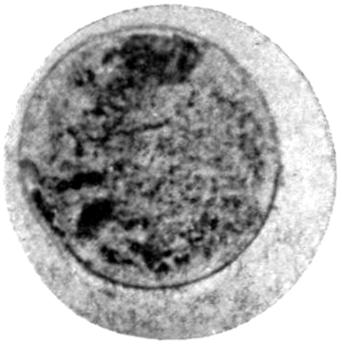

Plate I. 92

Plate II. 93

Plate III. 95